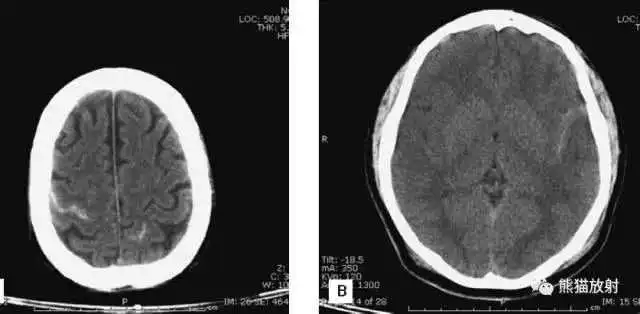

颅脑CT常用的三个窗(图A-C):

- 图A:骨窗(the bone window)

- 图B:脑窗(the brain window)

- 图C:血窗(the blood window)

图A:骨窗;主要用于明确骨折、窦腔病变、颅内积气。

图B:脑窗;可清晰显示灰白质,可发现中风的早期征象或其他导致脑水肿等表现的病变。

图C:血窗;更利于显示硬膜下或颅内出血。

本例表现:骨窗示:右顶骨骨折;三个窗均示:软组织水肿并皮下积气;血窗:少量硬膜下血肿。